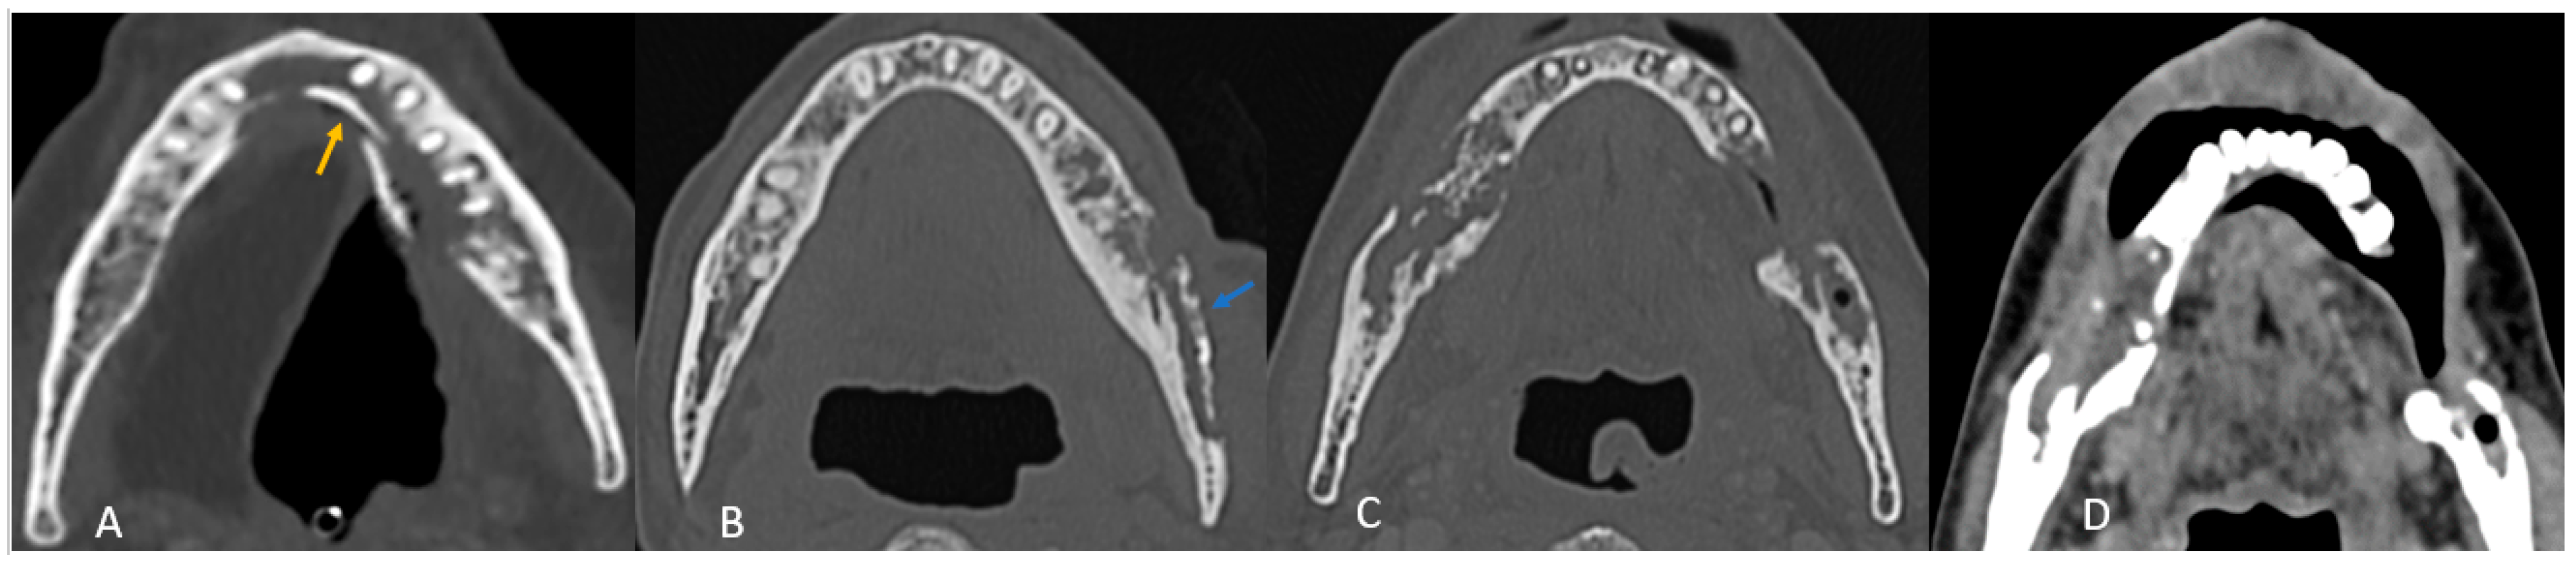

• Mandibular involvement was categorized as focal (<1/4th of hemi-mandible) in 63% or diffuse (larger area) (Figure 2A,B). Thirteen patients (37%) showed abnormalities extending across the midline. No significant associated soft tissue was noted compared to the bone erosion, and it was predominantly isoenhancing compared to the muscle (97%).

Figure 2. (A) Axial CT image of focal ORN along the resected margin in a case of segmental mandibulectomy. (B) Sagittal CT image of diffuse ORN in case of marginal mandibulectomy. There is bone resorption, coarse, sparse trabeculae, destruction of cortex, fragmentation (blue arrow), and intraosseous gas (orange arrow) present.

B. CT Imaging Findings in ORN

All patients exhibited trabecular and cortical resorption, with resultant bone fragmentation in 83% of cases (Figure 3A–C). Small pieces of bone separated from the main bone were termed as fragmentation (Figure 3A). A dense isolated fragment was termed as sequestration: this was seen in 29% of patients (Figure 3B). Intraosseous gas was seen in six cases as late-stage findings post-fragmentation, and five out of these had sequestration. Sclerosis was observed in 86% (n = 30) of cases and was heterogeneous in 23 cases (77%) and relatively homogeneous in 7 cases (23%). No correlation was found between sclerosis and fragmentation. (Table 1).

Figure 3. Axial CT images showing patterns of bony involvement in ORN. (A) Maximum bone alterations along the lingual cortex (with fragmentation—orange arrow) in a treated case of tongue carcinoma. (B) Maximum changes seen along the buccal cortex in a treated case of buccal carcinoma. (sequestrum—blue arrow). (C) Treated case of carcinoma of the base of tongue with ORN involving the posterior aspect of the body and the angle of the mandible. (D) Treated case of oropharyngeal carcinoma with ORN at both the angles of the mandible and iso-enhancing soft tissue at the site of bony involvement.

D. Patterns of ORN Based on Primary Tumor Site

In most cases (n = 30; 86%), the site of maximum bone involvement was close to the primary, like the focal ORN at the resected margin, and the pattern of bone involvement was predictive of ORN (Figure 3A–D).

Buccal mucosa/alveolus carcinoma: involvement of the adjacent mandible and ipsilateral maxilla was common, with bone changes predominantly observed at the primary site (Figure 3A).

Segmental mandibulectomy cases exhibited ORN at the cut margin and ipsilateral maxilla, with involvement of the buccal cortex more common than the lingual cortex (Figure 2A):

Anterior tongue carcinoma (Figure 3B) showed isolated diffuse mandibular involvement, with predominant lingual cortex involvement (unlike buccal or alveolar carcinoma).

Oropharyngeal and laryngeal carcinoma (Figure 3C,D): typically involved the angles of the mandible and adjacent posterior body/ ramus with sparing of the remaining mandible.